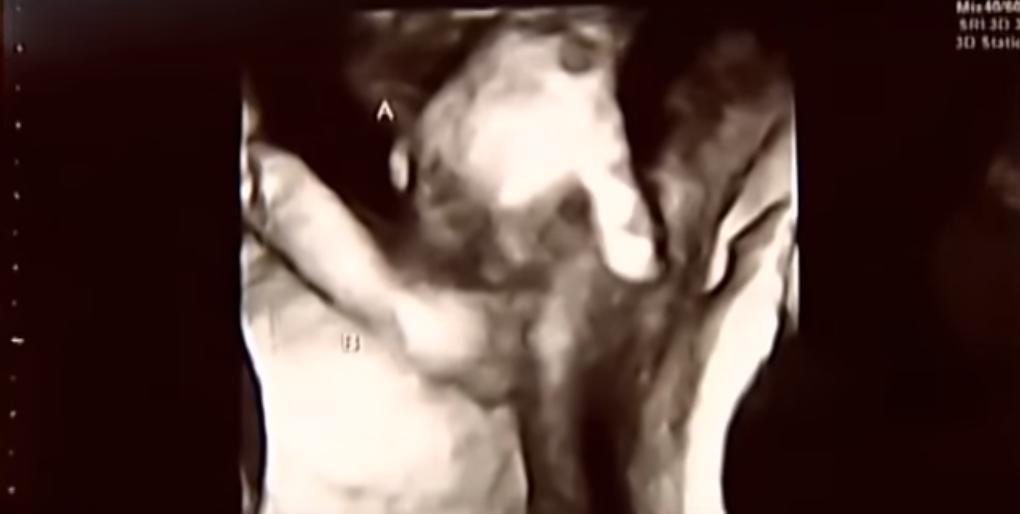

Cette échographie très émouvante de deux jumeaux se tenant la main fait actuellement le tour du web.

Sur leur dernière échographie 3D, les jumeaux Mason et Madelyn, un garçon et une fille, se tiennent la main. Et ce n’est pas que leur similitude génétique qui a provoqué ce rapprochement in utero : Mason souffre d’une malformation cardiaque et cérébrale et pourrait ne pas survivre à l’accouchement selon les médecins.

"La plupart des jumeaux se battent et se tapent sur les échographies. Mais elle nous a dit [la gynécologue] qu’avec nos jumeaux c’était différent : l’un se montrait particulièrement protecteur envers l’autre", a déclaré Brittani McIntire, la maman des jumeaux au média américain Kwch, poursuivant : "[Madelyn] est la seule qui peut-être là, se tenir près de lui. C’est réconfortant de penser que s’il nous quitte, il ne sera pas seul."